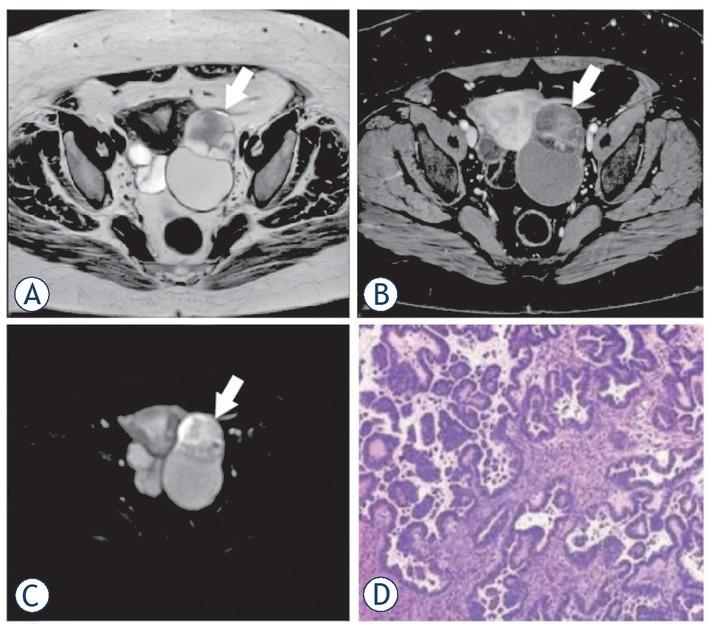

Figure 3